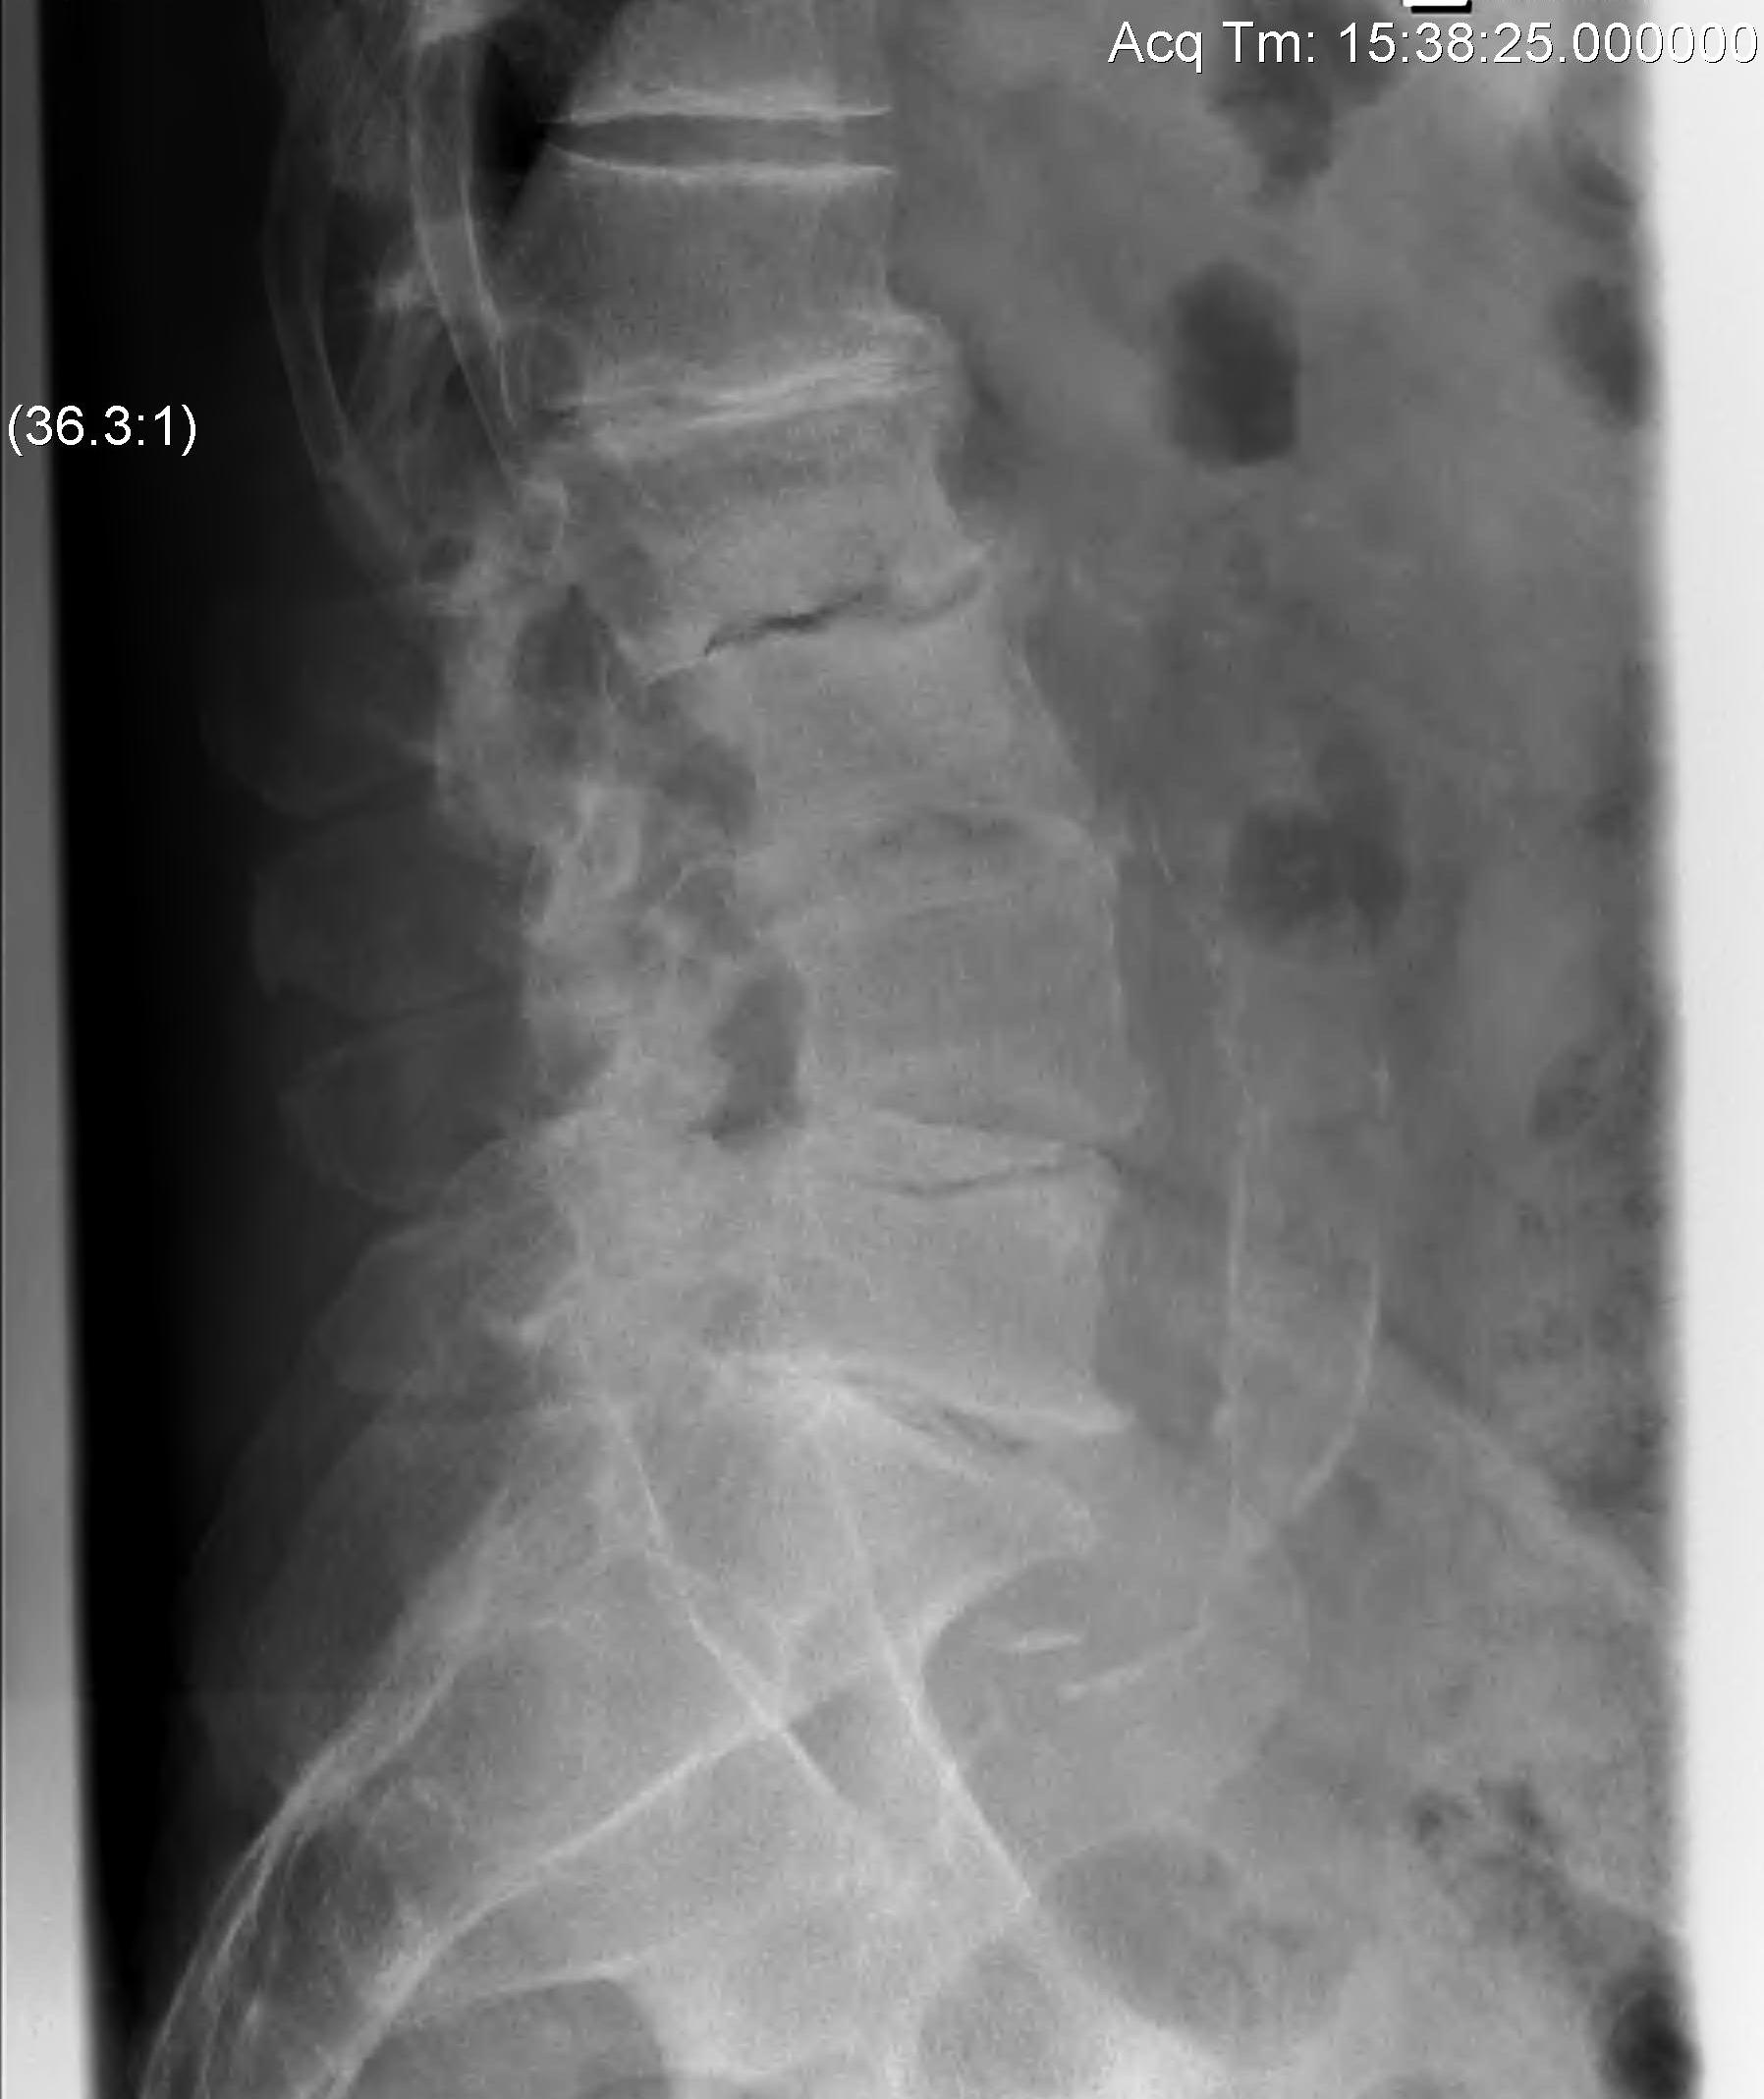

X-ray